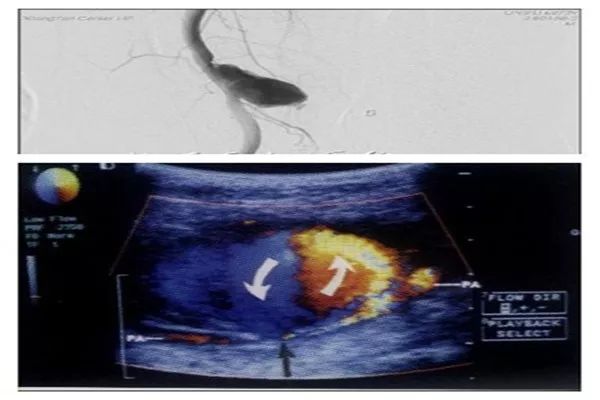

4. 假性动脉瘤

经皮穿刺以后动脉局部出血、血液通过动脉壁裂口进入血管周围组织,形成一个或多个腔隙(瘤腔)。病理表现为收缩期动脉血液经过载瘤动脉与瘤腔之间的通道(瘤颈部)流入瘤腔内,舒张期血流回流到动脉内。

影响假性动脉瘤的形成主要有5种因素,列举如下。

(1)穿刺部位偏低,位置越低越容易形成假性动脉瘤;

(2)动脉导管或鞘管的型号过大,尤其是导管(鞘)口径≥8 F者;

(3)技术不熟练及压迫不当;

(4)术中及术后使用抗凝、 抗血小板或溶栓药物;

(5)术后过早活动。

处理假性动脉瘤的方法有超声引导下注射凝血酶、超声引导下局部压迫、置入弹簧圈、外科手术修补。假性动脉瘤发现得越早,采用局部压迫的处理方法越好。

图5. 假性动脉瘤影像。